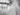

На рентген снимке видно: зуб 28 упирается в корни зуба 27, что привело к рассасыванию корневой системы.

Оба зуба были удалены, произведена костная пластика.

Через 3, 4 месяца в область 26 и 27 буду установлены импланты.

Уровень сложности 5/10

Время работы 45 мин.